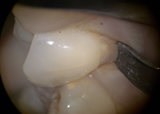

下の写真はくさび状の欠損を修復する際に使われるクランプです。

下の写真のようにこのクランプを使用しないできちんと防湿して材料を詰めることはできません。

材料の仕上げをしているところ。

材料の仕上げをしているところ。